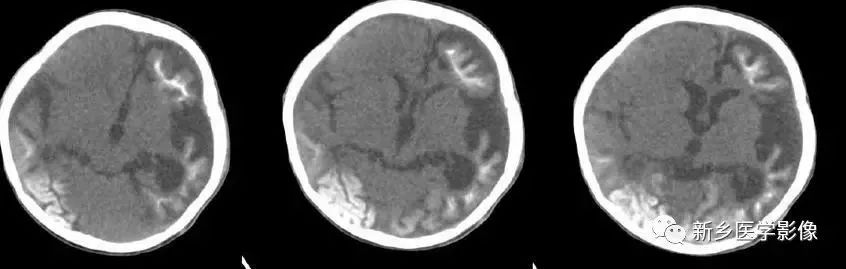

❸ 脑三叉神经血管瘤病

又称为脑-颜面血管瘤综合征。CT平扫以一侧半球脑实质内脑回样、轨道样、弧带状或锯齿状钙化为特征。由于受累侧血供障碍,常引起脑实质萎缩。所以可以表现有:患侧侧脑室扩大、颅腔变小、颅板增厚。特征是脑内可见典型钙化及临床三叉神经分布区有紫红色血管痣。